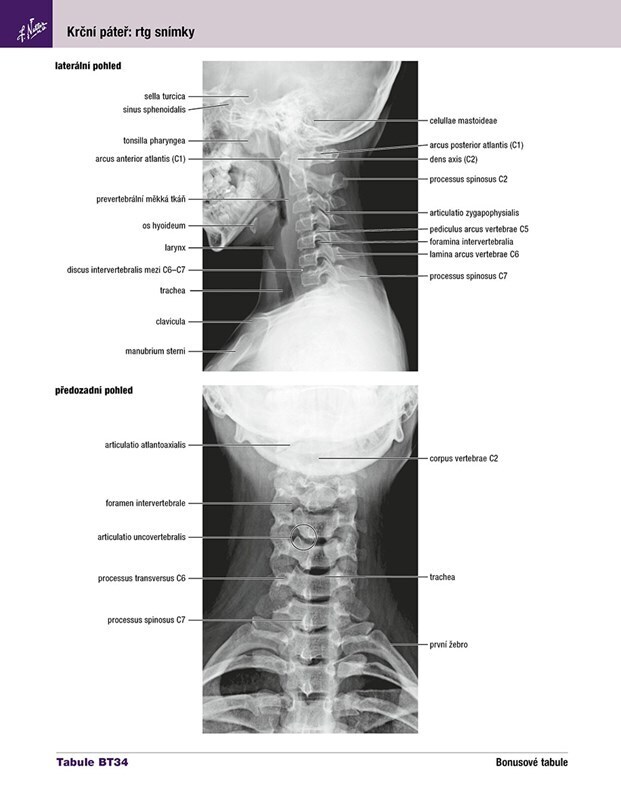

Netterův anatomický atlas člověka - Překlad 8. vydání

Frank H. Netter

Pro studenty a zdravotnické pracovníky, kteří studují anatomii, účastní se pitev či si osvěžují své znalosti, je tento anatomický atlas nenahraditelnou pomůckou. Představuje lidské tělo oblast po oblasti, v jasných a brilantních detailech, z pohledu klinického lékaře. Mezi ostatními je...